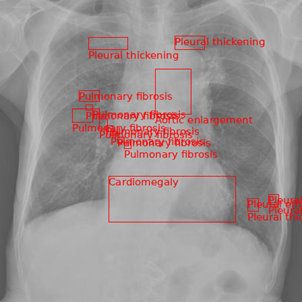

Figure 4 shows an example with many abnormalities and multiple global labels. The model accurately predicts ’Pneumonia’ and ’Other disease’, but hallucinates an additional global label of ’Tuberculosis’. The model accurately predicts some of the local abnormalities with great accuracy such as the mediastinal shift at the top and pleural effusion on the right lung. Apart from this, the model does hallucinate pleural thickening and pulmonary fibrosis in the left lung and aortic enlargement while missing the infiltration and pneumothorax. Despite this, the model performs well for this more ”difficult” data point.

Finally, Figure 5 is an example of the model hallucinating abnormalities to the extreme. For what is a simple example of a lung tumor, the model outputs tons of incorrect abnormalities. When this occurs, the model should be re-run to get more accurate results as it is obvious in this case that the model output abnormalities are incorrect. However, this case could be an indicator for the radiologist that there is some sort of abnormality in the chest X-ray. Despite this, the model does accurately predict the aortic enlargement and that there is an ’Other disease’ separate from the lung tumor that the model did not find.

Refer to caption

(a) Pneumonia, Other diseases (Test Labels)

(b) Pneumonia, Tuberculosis, Other diseases (Model Outputs)

Figure 4. Qualitative comparison between test labels and model output for multiple abnormalities.

(a) Lung Tumor, Other diseases (Test Labels)

(b) Other diseases (Model Output)

Figure 5. Qualitative comparison between test labels and model output showing multiple hallucinations.